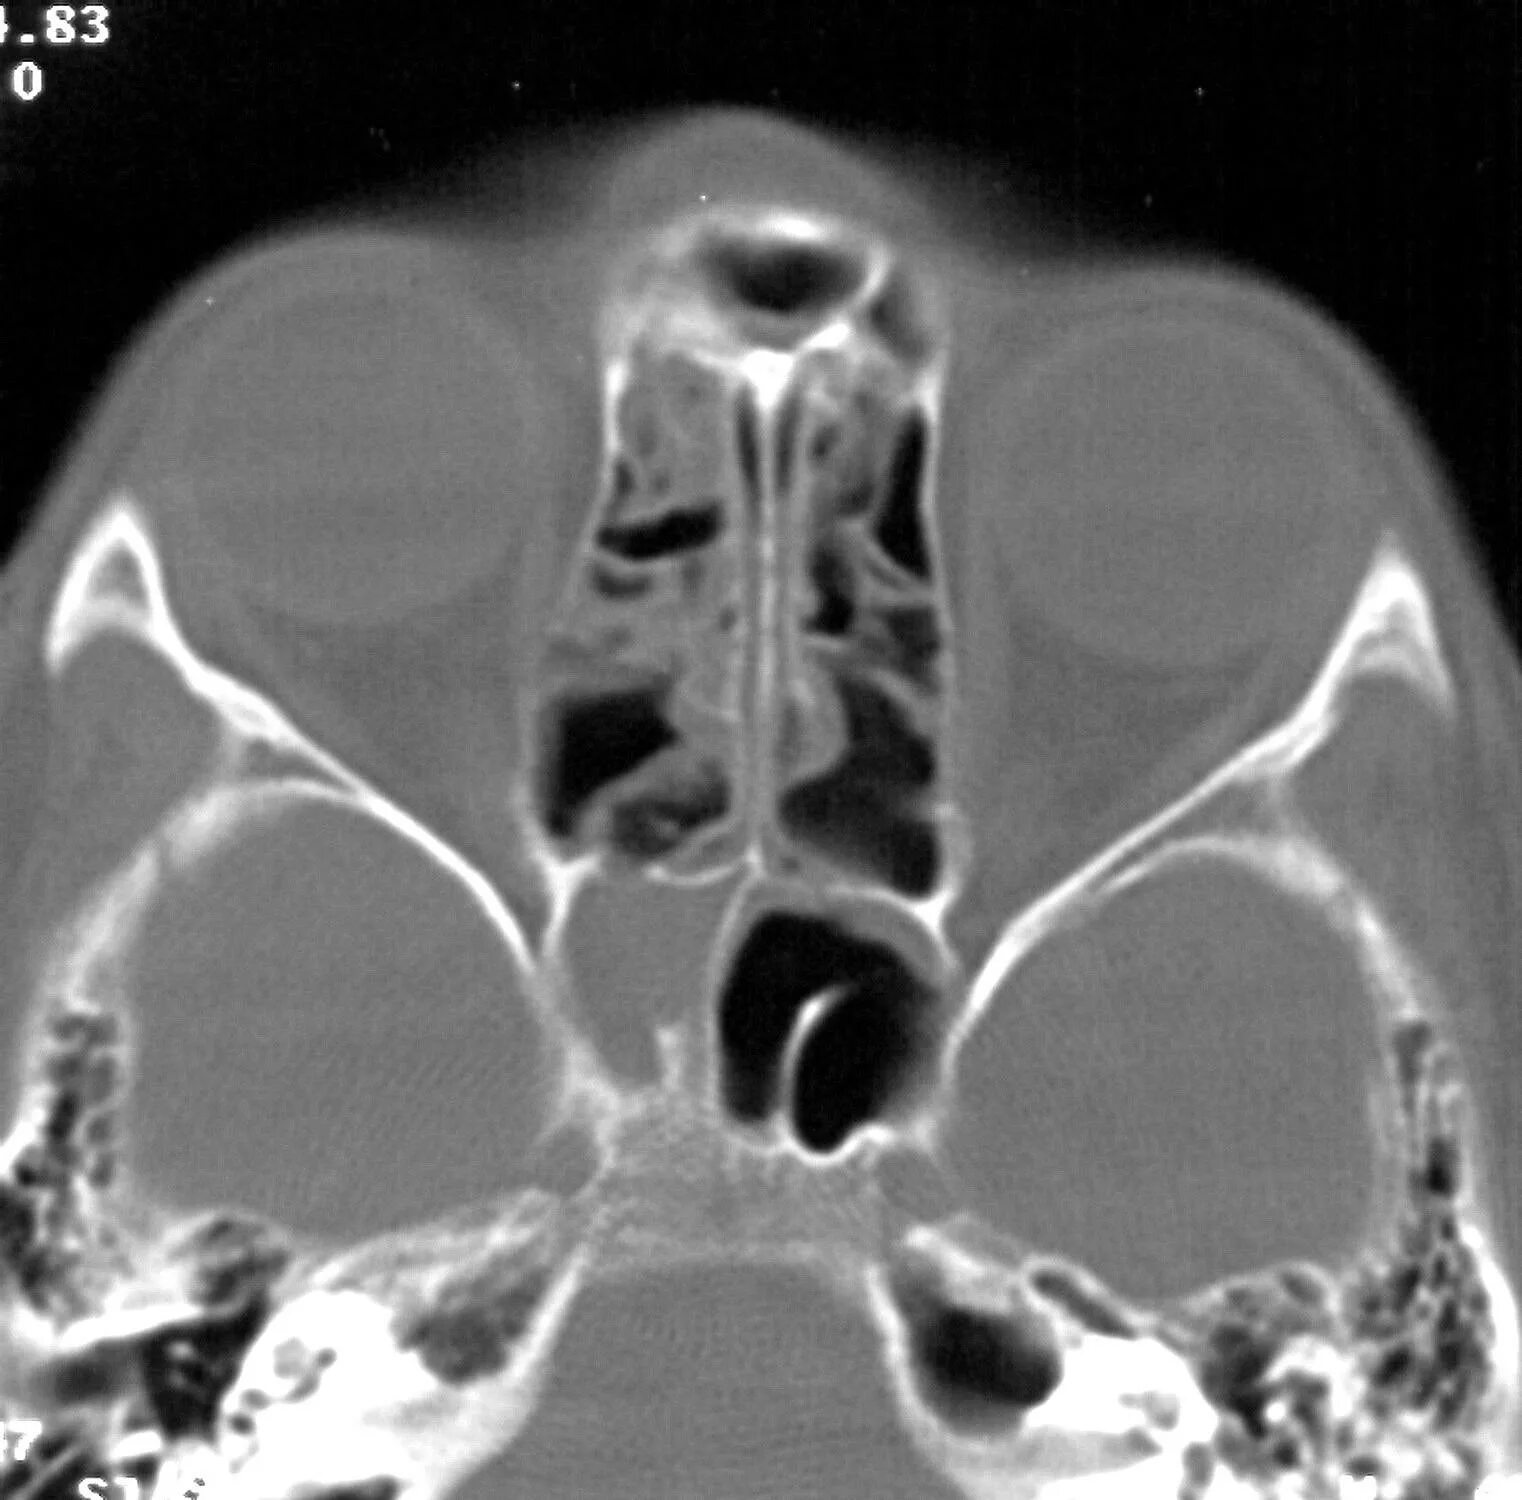

Сфеноидит симптомы